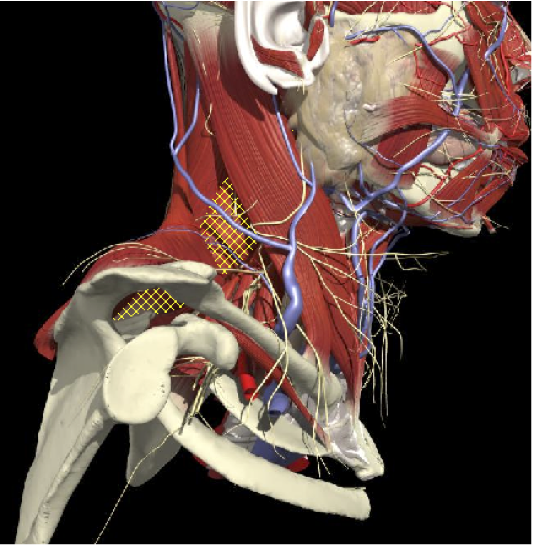

ACCURACY OF MUSCLE LOCALIZATION

- Muscles deep

- Not easily identified by surface landmarks

- Not palpable on examination

ACCURACY OF LOCALIZATION - SCALENES

ACCURACY OF LOCALIZATION LEVATOR SCAPULAE

LOCALIZATION OF MUSCLES IN DEEPER LAYERS

Layer 1

Layer 2

Layer 3

Splenius Capitis

Semispinalis Capitis

Longissimus Capitus

Semispinalis Cervicis

ACCURACY OF LOCALIZATION – DEEPER LAYERS

INJECTION SITES